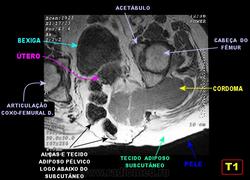

Сакральная хордома. Д-р Марсело Сенна Ксавье де Лима, Paul Roland Kaleff, и Антонио Рожерио del'Arco Roth Аугусто Варгас. Рецидив. Часть крестца была удалена ранее. Пнд, 27/11/2017 - 21:03 #1 Катенёв Валенти... Не на сайте Был на сайте: 7 лет 4 месяцев назад Зарегистрирован: 22.03.2008 - 22:15 Публикации: 54876 Внутричерепная хордома. http://pubs.rsna.org/doi/full/10.1148/rg.234025176 Пнд, 09/07/2018 - 20:44 #2 Катенёв Валенти... Не на сайте Был на сайте: 7 лет 4 месяцев назад Зарегистрирован: 22.03.2008 - 22:15 Публикации: 54876 Продолжение. Приложения: